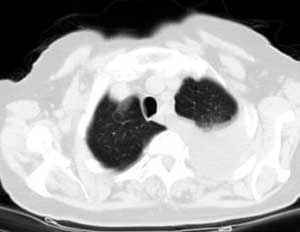

标题: CT0563:病历讨论,胸膜间皮瘤?

测ct值3-6hu,

既然ct值是3-6hu,还不如考虑包裹性积液。

请上传纵隔窗。目前还是支技包裹性积液(明显梭形),即使是间皮瘤并积液也少梭形的。

从图片看,包裹性积液好象更合理,梭形,ct值3-5hu(在哪看到的?);胸膜间皮瘤如此规则,不多见。

左侧背部胸膜肥厚,伴包裹性积液,不考虑间皮瘤.

同意以上各位的高见,首先考虑包裹性积液,1.胸膜间皮瘤积液量一般较大,以游离性积液更为常见,2.可以看到增厚的胸膜结节